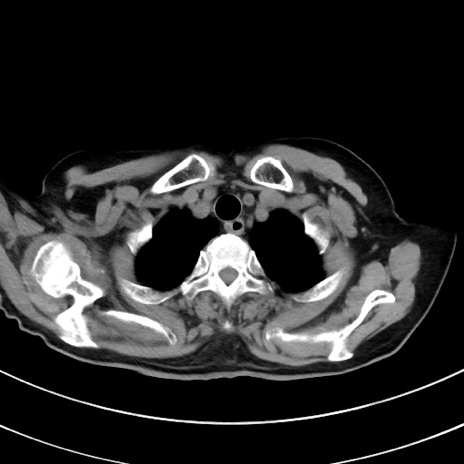

冠状断像

症例33(横断像)

【症例】70歳代 女性

【主訴】心窩部痛

【現病歴】延髄病変の精査・加療にて神経内科入院中。本日より心窩部痛あり。

【身体所見】右下腹部を中心に圧痛と反跳痛あり。

【データ】WBC 10900、CRP 0.02